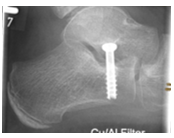

Arthrorise mit Calcaneus-Stoppschraube

Diese elegante und effektive Operationsmethode ist bei Kindern zwischen 8 und 12 geeignet, um selbst deutliche Fehlstellung durch Lenkung der körpereigenen Stellmechanismen (Propriozeption) zu korrigieren. Hierbei wird eine Schraube in das Fersenbein eingebracht, um eine übermäßige Verdrehung des Fersenbeins gegenüber dem Sprungbein zu verhindern.

Die Kinder können wenige Tage nach der Operation ohne Schiene voll belasten. Der Fadenzug erfolgt nach 12-14 Tagen. Verordnungen für Physiotherapie sind meist nicht sinnvoll, allerdings sind manchmal Anwendungen für Lymphdrainage notwendig. Die Kinder sollten ein bis zwei Wochen nach der Operation für ca. 10min bis zu dreimal täglich auf der Ferse und den Zehenspitzen gehen. Sollten hierbei Schmerzen bestehen, sollte solange damit gewartet werden, bis dieses schmerzfrei möglich ist. Wenn die Kinder im Alltag beschwerdefrei sind, können sie nach Ablauf von vier Wochen Fahrrad fahren und schwimmen. Auf Lauf- und Kontaktsportarten sollten die Kinder mindestens zwei Monate verzichten. Die Schraube muss nach drei Jahren wieder entfernt werden. Die Fehlstellung bleibt trotzdem korrigiert.